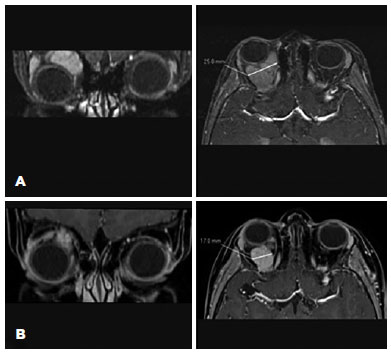

One year after achieving anatomical stability, the patient returned to the clinic due to increased proptosis and discomfort in the right eye. He had developed severe proptosis with hypotropia of the right eye and accompanying eyelid edema (Figure 1A). Visual acuity, pupillary reflex, and extraocular movements were preserved, and intraocular pressure was normal.

Treatment with oral prednisone (initial dose: 30 mg) was initiated, and MRI was repeated. Imaging revealed an increase in the lesion size (dimensions: 25 × 31 × 33 mm) accompanied by intralesional bleeding (Figure 2A).

Three months later, the proptosis and hypotropia had subsided, and the patient was asymptomatic. In addition, the palpebral edema had resolved (Figure 1B), and the optic nerve remained normal.

The MRI results revealed the presence of a lesion with reduced size (dimensions: 17 × 15 × 15 mm) compared with that measured in the previous imaging analysis (Figure 2B). The patient did not develop any treatment-related side effects; at the last visit; the levels of sirolimus in his blood were 6.2 ng/ml.